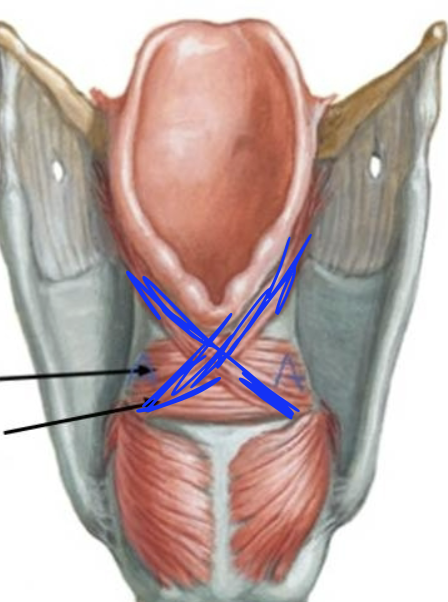

What is this muscle?

Oblique arytenoid (pull apex medially, assist in adducting VF)